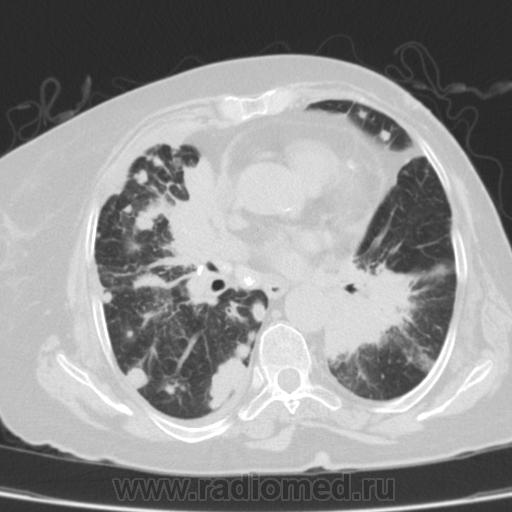

Метастатическое поражение легких.

Пожилая женщина, 76 лет находится на стац.лечении, провели СКТ дообследование.  Сопут- сr левой молочной железы. Такие множественные

поражения  в легких встречаются не часто.

Раннее несколько лет назад оперирована по поводу рака левой молочной железы.

Ну да, неспокойная работа, один тяжелее и  интересней другого. На обзорной рентгенограмме было всё видно прекрасно. Но терапевты направили, а я и не отказалась, чтобы в следующий раз знать- какие они бывают вторичные поражения легких.

Не всё на снимках видно. Многое осталось бы за кадром.